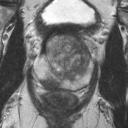

We present a novel technique to discover and exploit weak causal signals directly from images via neural networks for classification purposes. This way, we model how the presence of a feature in one part of the image affects the appearance of another feature in a different part of the image. Our method consists of a convolutional neural network backbone and a causality-factors extractor module, which computes weights to enhance each feature map according to its causal influence in the scene. We developed different architecture variants and empirically evaluated all of our models on two public datasets of prostate MRI images and breast histopathology slides for cancer diagnosis. To confirm our quantitative results, we conduct ablation studies and investigate the explainability of our models via class activation maps. Our findings show that our lightweight block extracts meaningful information and improves the overall classification, together with producing more robust predictions that focus on relevant parts of the image. That is crucial in medical imaging, where accurate and reliable classifications are essential for effective diagnosis and treatment planning.